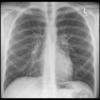

Normal PA

24 yo male